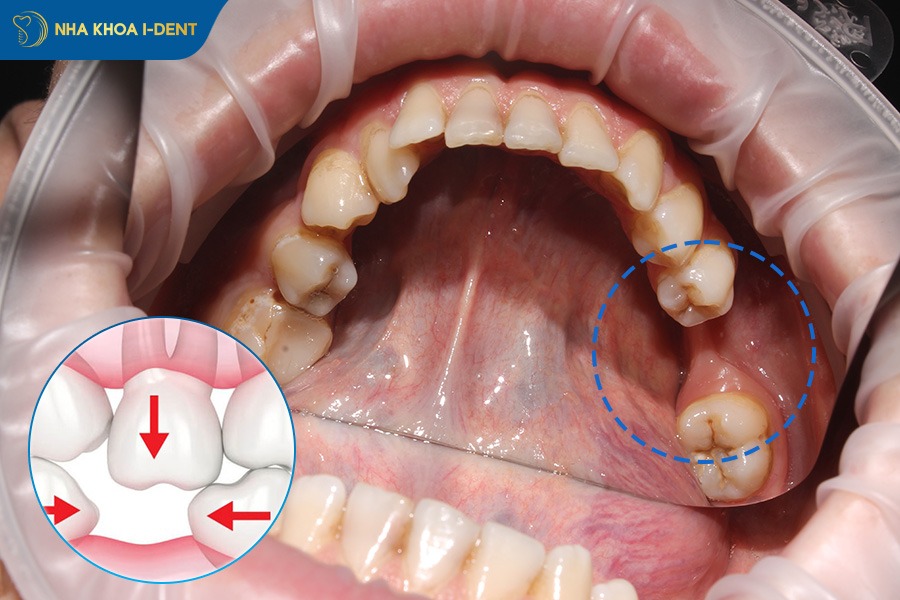

2.2. Xô lệch răng và sai lệch khớp cắn

Mất răng gây ra hiện tượng xô lệch các răng còn lại trong hàm và rối loạn khớp cắn. Các răng trên cung hàm tạo thành một thể thống nhất nâng đỡ nhau trên cung hàm và phân bổ đều lực nhai. Khi mất một răng thì răng ở hàm đối diện cũng không còn sự nâng đỡ, dần trồi lên hoặc tụt xuống để tìm điểm tiếp xúc, làm hỏng khớp cắn tự nhiên. Gây ảnh hưởng hoạt động nhai cắn và đau nhức khi nhai, ảnh hưởng lâu dài đến chức năng nhai.

Mất răng khiến lực nhai không phân bổ đều. Hai răng bên cạnh răng mất sẽ mất điểm tựa và có xu hướng dịch chuyển hoặc nghiêng về phía khoảng trống mất răng. Lâu dần tạo các khoảng trống mới cho các răng khác tiếp tục xô lệch, gây chen chúc, sai lệch khớp cắn và ảnh hưởng đến thẩm mỹ. Đặc biệt khi bị mất răng hàm thì khả năng bị lệch khớp cắn nặng hơn có thể dẫn đến liệt cơ hàm và lệch mặt.

Mất răng hàm khiến các răng khác xô lệch, làm sai lệch khớp cắn.